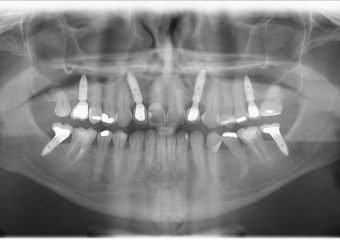

Raio X dos implantes e enxerto ósseo superior posterior

Raio X final